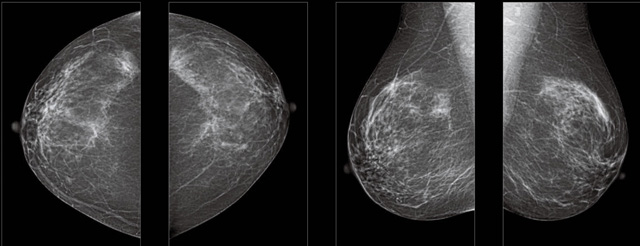

首先不同年齡階段的乳腺篩查頻次種類不一樣。青春期女性第二性征明顯發(fā)育開始,每個月進(jìn)行自我乳腺檢查。20-30歲的女性就不推薦進(jìn)行乳腺檢查,因為年輕女性的乳腺組織非常緊急。鉬靶X光線等檢查的射線不能辨別腫塊跟腺體。身體就白吸收了輻射,影響了身體健康。每個月自檢一次就是在洗澡時候,對著鏡子看看乳房外觀正常,皮膚潰爛、腫塊、顏色改變、再摸一下有沒小疙瘩。乳腺高危人群,特別是有乳腺CA遺傳傾向的女性,乳腺導(dǎo)管跟小葉不典型增生,原位癌。30歲前有乳房放療的女性。乳腺癌篩查可以把年齡提前到40歲前。40到70歲的女性可以在適合的機(jī)會篩查。

采用影像檢查技術(shù)來發(fā)現(xiàn)疑似特定病檢查跟人群的普查。一到兩年進(jìn)行一次X光線的乳腺檢查。記過是C或者D型,可以加上B超協(xié)同。還可以一年一次核磁共振MRI檢查。70歲以上的女性認(rèn)為絕經(jīng)的女性是比較安全的。實際上也有乳腺癌的風(fēng)險。65歲以上風(fēng)險也很大。也是需要進(jìn)行機(jī)會性篩查。